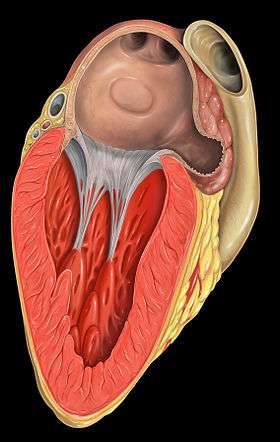

Anterior (frontal) view of the opened heart. White arrows indicate normal blood flow. (Mitral valve labeled at center right.) | |

Section of the heart showing the ventricular septum. (Bicuspid valve visible at center.)

Section of the heart showing the ventricular septum. (Bicuspid valve visible at center.)

Cross-sectional view of mitral valve between left atrium (upper chamber) and left ventricle (lower chamber), which shows parts of walls of left atrium and left ventricle that are next to the mitral valve. Mitral valve

Mitral valve